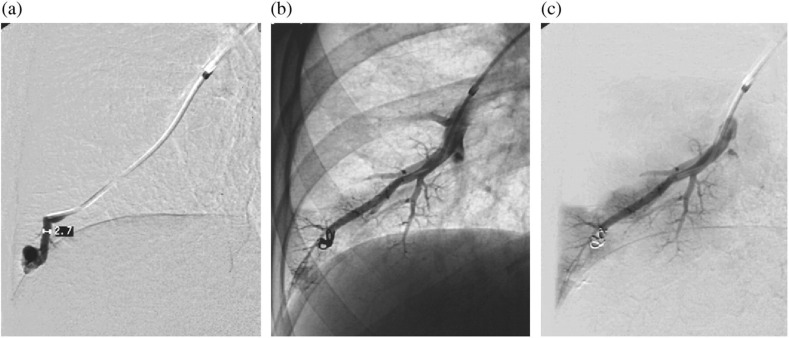

肺动脉动静脉畸形(pavm)的供血动脉长度为3mm或以上,已被证明与矛盾栓塞和严重的神经系统并发症有关。因此,通常建议闭塞这种大小的供血动脉,而较小的供血动脉通常不予治疗。然而,神经系统并发症也被描述在小的pavm患者中,并且不可能根据供血动脉的大小对风险进行分层,因此没有证据表明3mm是可能引起并发症的供血动脉的临界大小。此外,众所周知,随着时间的推移,pavm及其供血动脉可能会扩大。此外,栓塞小供血动脉将最大限度地减少矛盾栓塞的风险,并减少对这些患者进行CT随访控制的需要。两个病例证明了栓塞小供血动脉的可能性。

Pulmonary arteriovenous malformations (PAVMs) with feeding arteries of 3 mm or more have been shown to be associated with paradoxical embolization and serious neurologic complications. Therefore it is generally recommended to occlude feeding arteries of this size, while smaller feeding arteries often are left untreated. However, neurologic complications have also been described in patients with small PAVMs, and it has not been possible to stratify risk by size of feeding artery and thus there is no evidence that 3 mm is the critical size of the feeding artery potentially giving complications. Further, it is well-known that with time PAVMs and their feeding arteries may enlarge. Also, embolization of small feeding arteries will minimize the risk of paradoxical emboli and reduce the need for CT follow-up controls in these patients. Two cases demonstrate the possibility to embolize small feeding arteries.